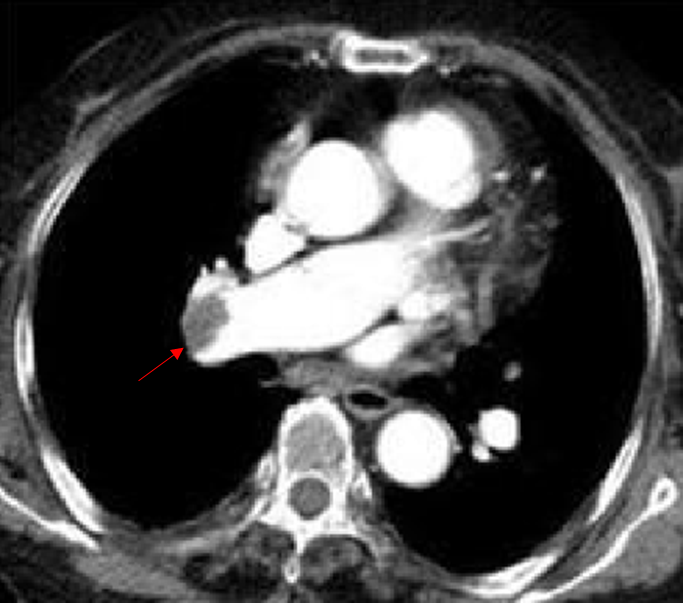

Img | CXR : 정상 Chest CT : 우폐동맥 혈전 |

• CT에서 폐동맥 혈전이 보이므로 폐색전증으로 진단할 수 있다.